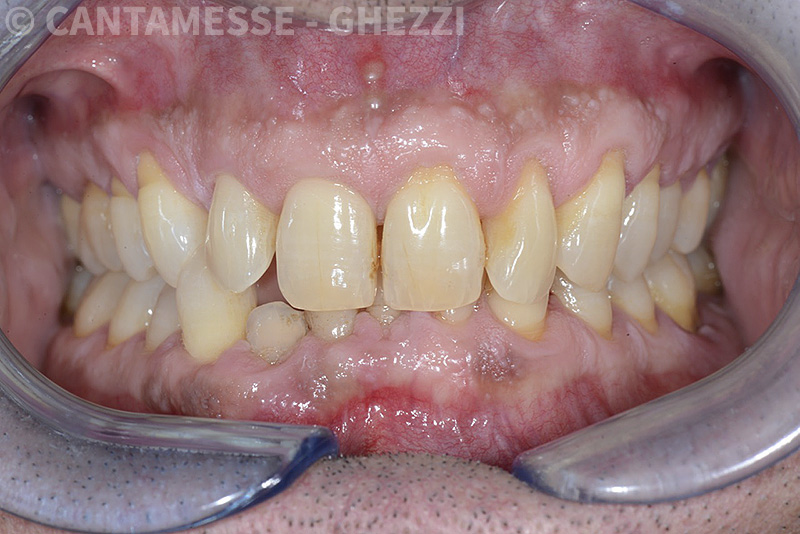

PREMESSA: in seguito all’estrazione dell’incisivo laterale superiore di destra, resasi necessaria per cause batteriche, si decide di affrontare il caso con il posizionamento di un impianto in sostituzione dell’elemento mancante dopo guarigione del sito infetto. Con tecniche rigenerative sia dei tessuti ossei mancanti a causa dell’infezione pregressa, sia dei tessuti gengivali che appaiono inizialmente troppo spostati in alto, si ripristina una corretta morfologia delle parabole (contorni) gengivali e delle papille interdentali (triangoli di gengiva tra due denti vicini).

Vengono utilizzati 2 tipi di provvisori: il primo, cementato ai denti vicini, viene utilizzato dal momento dell’estrazione del dente fino ad impianto osteointegrato (circa 6 mesi); il secondo, avvitato direttamente all’impianto, ha una funzione di prova estetica ma soprattutto di guida per la maturazione dei tessuti gengivali peri-implantari portandoli verso la maturazione completa prima di posizionare la corona finale in disilicato di litio.